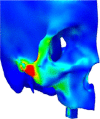

Results: The lack of maxillary boney support at the implant platform resulted in significant higher stress measured within the zygoma implant as well as the zygoma bone.

Conclusion: The maxilla is the primary support when zygoma implants are placed under functional loads. Quad-cortical stabilization of the zygoma implants and their cross-arch stabilization are recommended to reduce the degree of stress whenever possible.